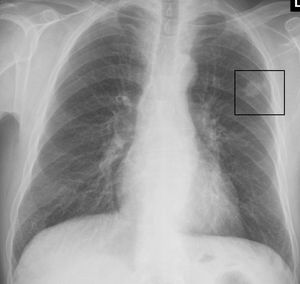

Google har en AI som kan upptäcka bröstcancer Gör detta bättre än mänskliga läkare Google har en AI som kan upptäcka bröstcancer Foto: Northwestern University in Chicago Googles AI-företag Deep Mind har utvecklat ännu en artificiell intelligens och deras senaste AI har man tränat upp för att upptäcka bröstcancer på patienters mammografi-bilder.I tester ska Deep Minds AI ha kunnat avgöra om en patient hade bröstcancer lika bra som professionella radiologer. I vissa fall där mänskliga läkare trott att patienten hade cancer eller hade missat att patienten hade cancer ska AI:n bättre ha kunnat diagnosticera patienten.Artificiella intelligenser som den Googles Deep Mind nu har tagit fram kommer sannolikt att bli vanligare inom vården i framtiden även om de än så länge inte används i någon direkt utsträckning. Än så länge är det även mänskliga läkare som har sista ordet när det kommer till att diagnosticera patienter men AI:s som den här kommer sannolikt att underlätta läkares arbete i framtiden. reuters.com Vetenskap, Medicin, google, deep mind, artificiell intelligens, cancer, bröstcancer, mammografi Google har en AI som kan förutspå om patienter får lungcancer Gör detta mycket bättre än läkare Tumnagel 59.3° 0 Google tar fram piller som kan upptäcka cancer Och andra sjukdomar Tumnagel 86.8° 0 Google hittar cancerceller i realtid Med ett AR-mikroskop Tumnagel 53.7° 0 60.1° 0 Wille Wilhelmsson Wille Wilhelmsson